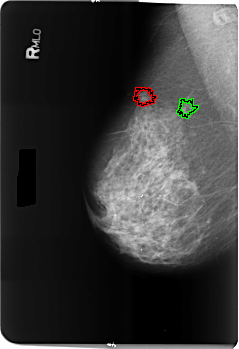

B_3513_1.RIGHT_MLO

FILE: B_3513_1.RIGHT_MLO.OVERLAY

TOTAL_ABNORMALITIES 2

ABNORMALITY 1

LESION_TYPE MASS SHAPE ARCHITECTURAL_DISTORTION MARGINS ILL_DEFINED-SPICULATED

ASSESSMENT 4

SUBTLETY 4

PATHOLOGY MALIGNANT

TOTAL_OUTLINES 1

BOUNDARY

ABNORMALITY 2